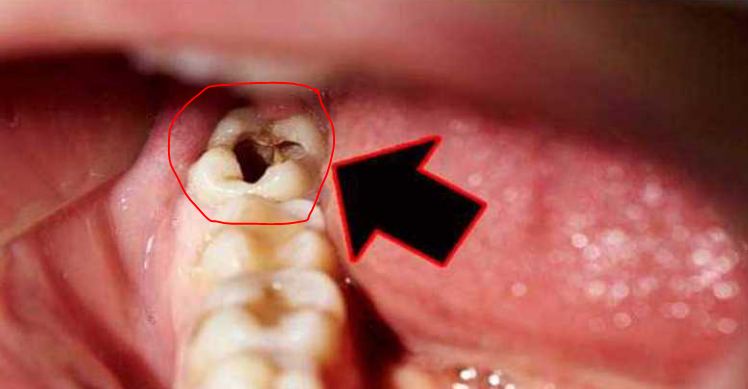

8. กุยช่าย ในกรณีที่ปวดฟันเพราะแมงกินฟัน ให้นำเมล็ดกุยช่ายมาคั่วให้เกรียมดำ จากนั้นนำมาบดให้ละเอียดละลายน้ำมันยางแล้วชุบสำลี ยัดในฟันที่เป็นรูโพรง ทิ้งไว้หนึ่งคืน จะสามารถฆ่าตัวแมงที่กินฟันได้